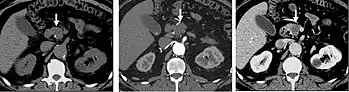

CT angiography (CTA) is highly effective for evaluation of the arterial system, and has largely replaced conventional angiography due to the lower risk profile and ability to survey the entire abdomen. Images are acquired after a rapid bolus of intravenous contrast material (3-7 cc/s) during the arterial phase (15–35 seconds after injection) when the concentration of contrast material in the arterial system is high (figures 3). Images are usually acquired using narrow collimation (<1 mm) and can be retrospectively reconstructed using dedicated 3-dimensional workstations and software. CTA is commonly used in the head and chest in the evaluation of pulmonary emboli, aneurysms, vascular malformations, dissection, bleeding and ischemia. Indications for early arterial phase imaging include: evaluation of aneurysms or dissections (cerebral, aortic, etc.), hepatic, splanchnic or renal arterial anatomy, and arterial imaging in liver or kidney transplantation. Single phase arterial imaging is often used in the evaluation of trauma patients either a complete chest/abdomen/pelvis examination with arterial phase imaging of the chest and portal venous phase imaging of the abdomen/pelvis or just a portal venous phase of abdomen and pelvis depending on the mechanism and severity of the trauma. CTA is also commonly performed in the abdomen and pelvis for evaluating vascular malformations and in the evaluation of bleeding. Mesenteric ischemia can also be evaluated using CT angiography. CTA of the abdomen and pelvis is often performed in combination with a CTA for evaluating the extremity vasculature.

Late arterial phase

The late arterial phase is timed to correspond to the peak concentration of contrast material in highly vascular tumors and is performed approximately 20–35 seconds after the injection of intravenous contrast. Early arterial phase imaging is predominantly utilized for angiography and will be discussed separately. Late arterial phase imaging is almost always performed in conjunction with other phases (e.g. portal venous phase) to allow more complete characterization of any identified abnormalities (figure 4). The primary indication for a late arterial phase is for the evaluation of hypervascular tumors of the liver such as hepatocellular carcinoma or hypervascular metastases (figure 4). Typical hypervascular tumors for which this would be used include: hepatocellular carcinoma; renal cell carcinoma; melanoma; carcinoid/neuroendocrine tumors; some sarcomas; choriocarcinoma; and thyroid carcinoma. Although a “hypervascular”, biphasic evaluation would generally be used for these patients, note that a single phase is often adequate for follow up imaging.